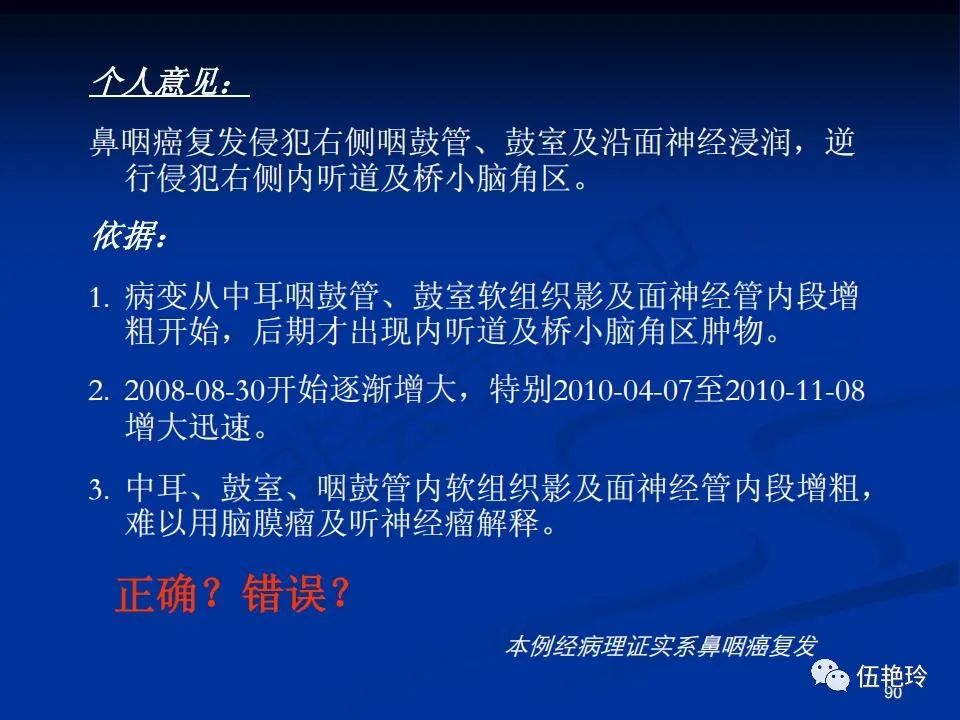

耳与面神经的解剖